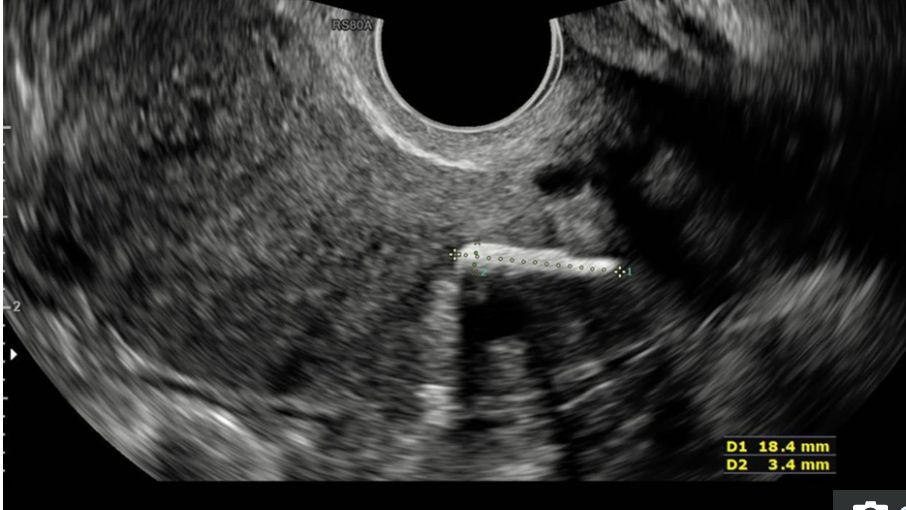

Mniej więcej rok później kobieta wróciła do kliniki ginekologicznej, skarżąc się na przewlekły ból w lewym boku i długie, bolesne okresy. Została zapisana na test barwnika, który miał sprawdzić, czy nie choruje na zespół policystycznych jajników (PCOS). W oczekiwaniu na operację pacjentka została poddana powtórnemu badaniu USG miednicy. Wtedy w tkance jej macicy odkryto ciało obce.

Ale dopiero podczas badania fizycznego i wykonania testu barwnika, okazało się, co jest przyczyną bólu i niemożności zajścia w ciążę. Lekarze wiedzieli, że kobieta przeszła aborcję chirurgiczną dwie dekady temu i doszli do wniosku, że ciałem obcym, które wykryto, jest kość płodu, która pozostała w łonie kobiety.

"Zatrzymanie kości płodu jest rzadkim, ale niedostatecznie zdiagnozowanym powikłaniem po aborcji. Nieleczona może powodować zaburzenia miesiączkowania i wtórną niepłodność" - napisano w raporcie.

Zauważono, że ani wcześniejszy rezonans magnetyczny oraz ultradźwięki nie wykryły kawałka kości, dlatego objawy kobiety były błędnie diagnozowane od lat.